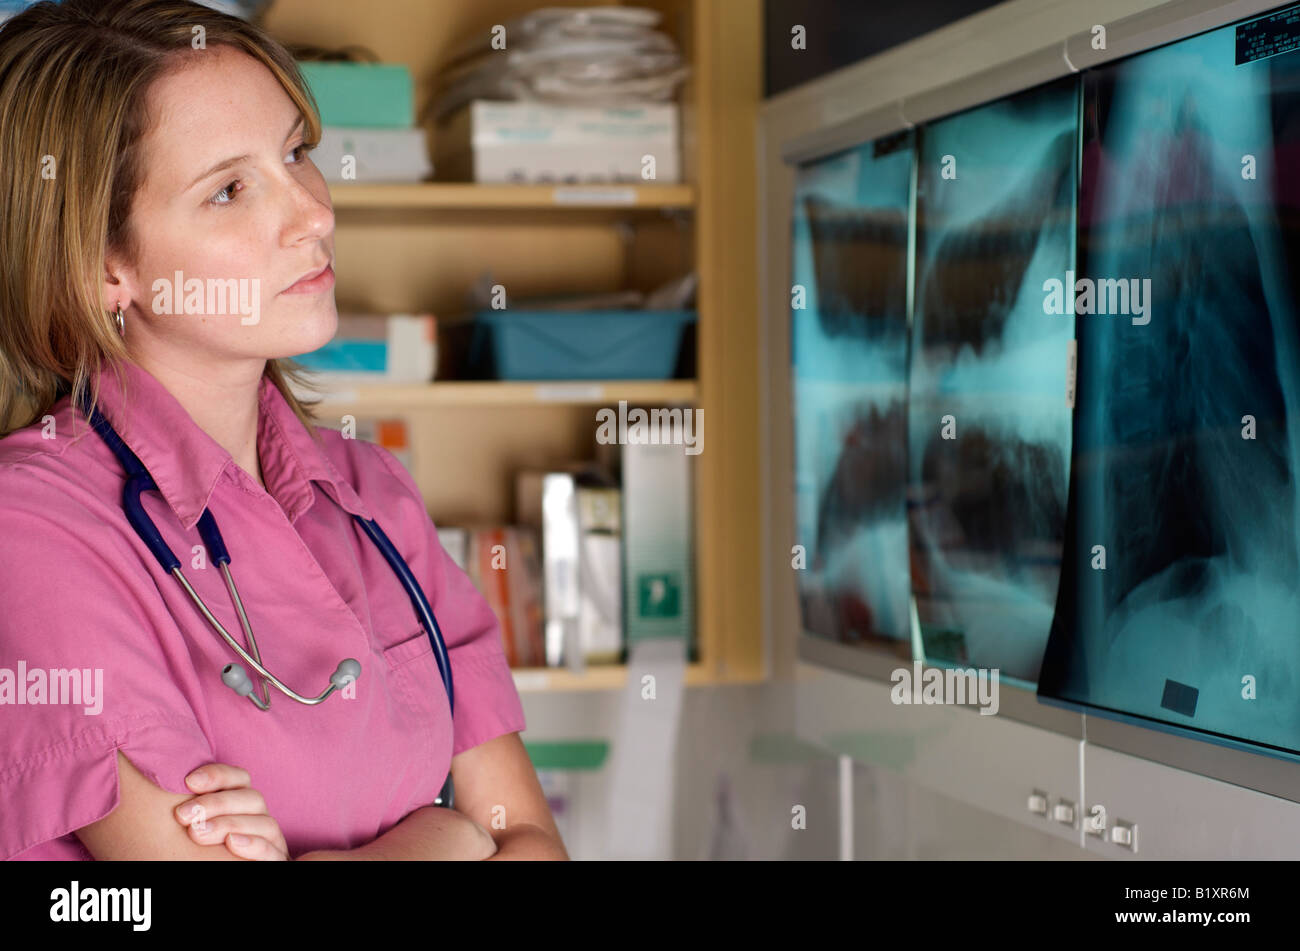

Dans scrubs infirmier stéthoscope avec examen de Xray. Paramètre d'arrière-plan de l'hôpital. Banque D'Imageshttps://www.alamyimages.fr/image-license-details/?v=1https://www.alamyimages.fr/photo-image-dans-scrubs-infirmier-stethoscope-avec-examen-de-xray-parametre-d-arriere-plan-de-l-hopital-18413996.html

Dans scrubs infirmier stéthoscope avec examen de Xray. Paramètre d'arrière-plan de l'hôpital. Banque D'Imageshttps://www.alamyimages.fr/image-license-details/?v=1https://www.alamyimages.fr/photo-image-dans-scrubs-infirmier-stethoscope-avec-examen-de-xray-parametre-d-arriere-plan-de-l-hopital-18413996.htmlRFB1XR6M–Dans scrubs infirmier stéthoscope avec examen de Xray. Paramètre d'arrière-plan de l'hôpital.